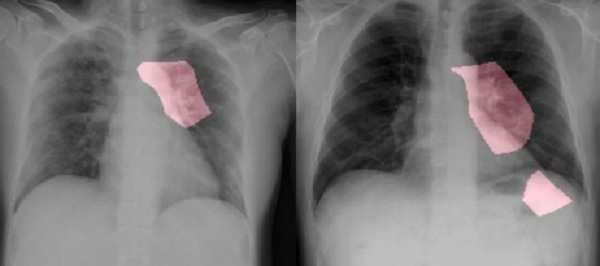

Các nhà khoa học tại Đại học Waterloo đã đưa ra phần mềm AI có thể phát hiện tốt hơn các bệnh nhiễm trùng từ tia X ngực. Công nghệ này không thể thay thế các thử nghiệm, nhưng nó có thể làm tăng hiệu quả sàng lọc.

AI chỉ đơn giản là nhìn vào các tia X phổi, tìm kiếm những bất thường sẽ phù hợp với những gì nhìn thấy ở bệnh nhân COVID-19. Bằng cách phân tích điều này ở các triệu chứng khác, bác sĩ có thể tiếp cận các chẩn đoán rất chính xác.